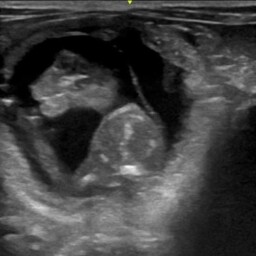

• Monitorowanie przebiegu ciąży (USG bardzo wysokiej jakości, RTG, badania hormonalne)

• Prowadzenie ciąż zagrożonych